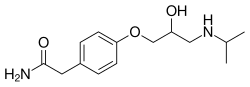

Selective beta-1 blocker

- Atenolol

- Metoprolol

Beta-1 blocker

Beta-1 blocker will stop the action of beta-1 receptor via occupying the beta-1 receptor without any activation.[5] The beta-1 receptor is a G-protein-coupled receptor with Gs alpha subunit as its main communication method.[5] By signaling Gs, adenylyl cyclase is recruited to activate a cAMP pathway, which potentiates the receptor.[5] This kind of receptor is located at the heart, kidney and adipose tissue.[5] Eventually, a higher cardiac output(or an increased amount of perfusion to organs) will be resulted.[5] Moreover, more renin is released from the kidney to produce more angiotensin II, increasing the blood volume.[5] Moreover, it encourages lipolysis in adipose tissue. Beta-1 blocker blocks the beta-1 receptor and stops the action mentioned above. (signaling Gs, thus activate cAMP pathway by recruiting adenylyl cyclase, leading to higher cardiac output, renin release and lipolysis)